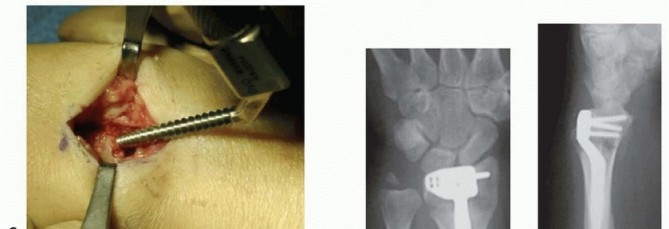

Fixation of Distal Radius Fractures using a Dorsal Intramedullary Device (Tornier) The fracture is exposed using a limited version of the incision detailed for placement of a dorsal plate ( TECH FIG 4A). The extensor retinaculum is incised just ulnar to the tubercle of Lister, exposing the EPL tendon. The EPL tendon is freed proximally and distally by incising the septum of the third dorsal compartment. The EPL tendon should then be transposed and protected for the rest of the surgical procedure. A scalpel is used to subperiosteally elevate the fourth and portions of the second extensor compartment in radial and ulnar directions. The dorsal cortex of the distal radius is exposed and room is created for seating of the extramedullary portion of the device.

TECH FIG 4 • A. A 2.5-cm dorsal incision is used for exposure. B. The awl is inserted through the fracture site after removal of the tubercle of Lister.

(continued)

The tubercle of Lister is removed, and an awl is used to create an entry point in the dorsal cortex ( TECH FIG 4B). This usually involves a portion of the fracture line. The canal is rasped until the rasp may be fully seated ( TECH FIG 4C). The implant is placed using the insertion device to control rotation ( TECH FIG 4D). Typically, the fracture reduces as the device is inserted and seated due to the buttress effect and three-point fixation of the implant within the canal. Lag screws are inserted as required, followed by a cover lock to create fixed-angle stability. Reduction and stabilization are confirmed radiographically ( TECH FIG 4E,F). Wound closure and splinting are as described earlier.

TECH FIG 4 •

C. A rasp is used to create a path for the implant. D. The implant is placed using the insertion device so as to control rotation during seating. E,F. An unstable metaphyseal distal radius fracture has been reduced and stabilized using a dorsal intramedullary device (Tornier Corp). (E,F: Copyright Thomas R. Hunt III, MD.)